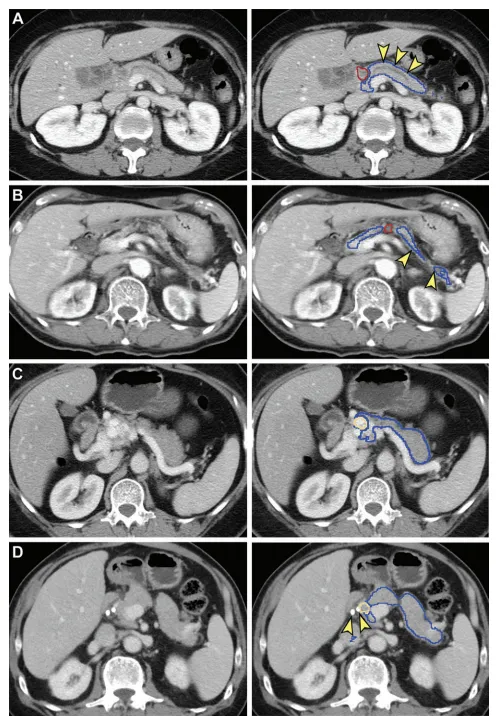

Figure 4: False-negative (A, B) and false-positive (C, D) tumor segmentation by the segmentation model. Blue and yellow outlines indicate normal pancreas and tumor segmented with the segmentation model, respectively. Images in the left column are original unannotated CT scans. (A, B) Tumors (red outline) were not segmented by the segmentation convolutional neural network. The upstream pancreas shows secondary signs of pancreatic cancer, including dilation of the pancreatic duct with abrupt cutoff (arrowhead in A) and parenchymal atrophy with dilation of the pancreatic duct(arrowhead in B). © Collateral veins secondary to idiopathic portal vein thrombosis were incorrectly segmented as tumor by the segmentation model. (D) Pancreatic parenchyma adjacent to biliary stents (arrowhead) placed for relieving obstructive jaundice from hepatocellular carcinoma was incorrectly segmented as tumor by the segmentation model.

图4:分割模型的假阴性(A, B)和假阳性(C, D)肿瘤分割。蓝色和黄色轮廓分别表示用分割模型分割的正常胰腺和肿瘤。左列图像是原始未标注的CT扫描。(A, B) 肿瘤(红色轮廓)未被分割卷积神经网络分割。上游胰腺显示胰腺癌的次要征兆,包括胰管扩张和突然截止(A中的箭头)以及胰腺实质萎缩和胰管扩张(B中的箭头)。© 由特发性门静脉血栓形成的侧支静脉被分割模型错误地分割为肿瘤。(D) 为缓解肝细胞癌引起的梗阻性黄疸而放置的胆道支架(箭头)旁的胰腺实质被分割模型错误地分割为肿瘤。